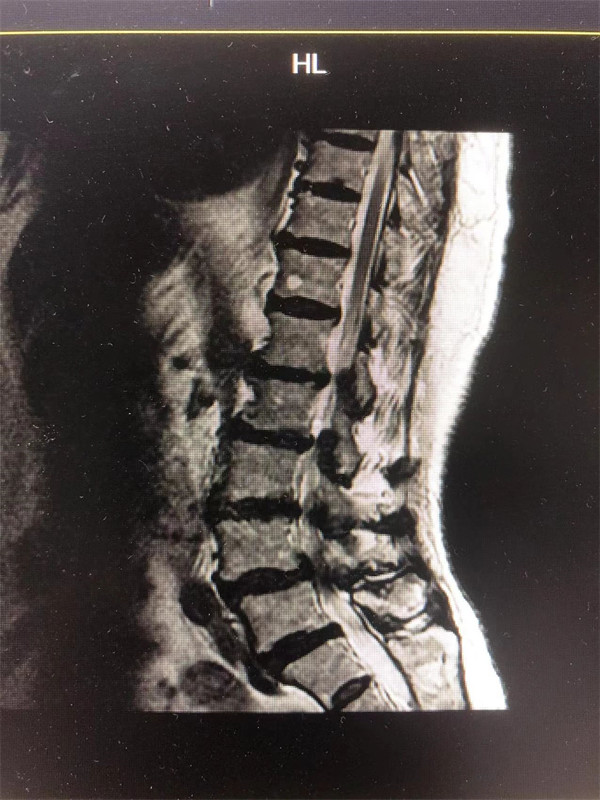

戈主任仔細詢問阿婆病情癥狀,綜合查體及MRI片情況,認為阿婆有明顯的腰椎滑脫,腰椎管狹窄,這是引發(fā)阿婆病痛的主要因素。

手術前↓

阿婆曾在院外多家醫(yī)院就醫(yī),被診斷為腰4椎體滑脫癥、腰椎管狹窄癥、腰椎間盤突出癥,外院予以止痛、理療、針灸等各種保守方式治療,病情未見明顯改善。